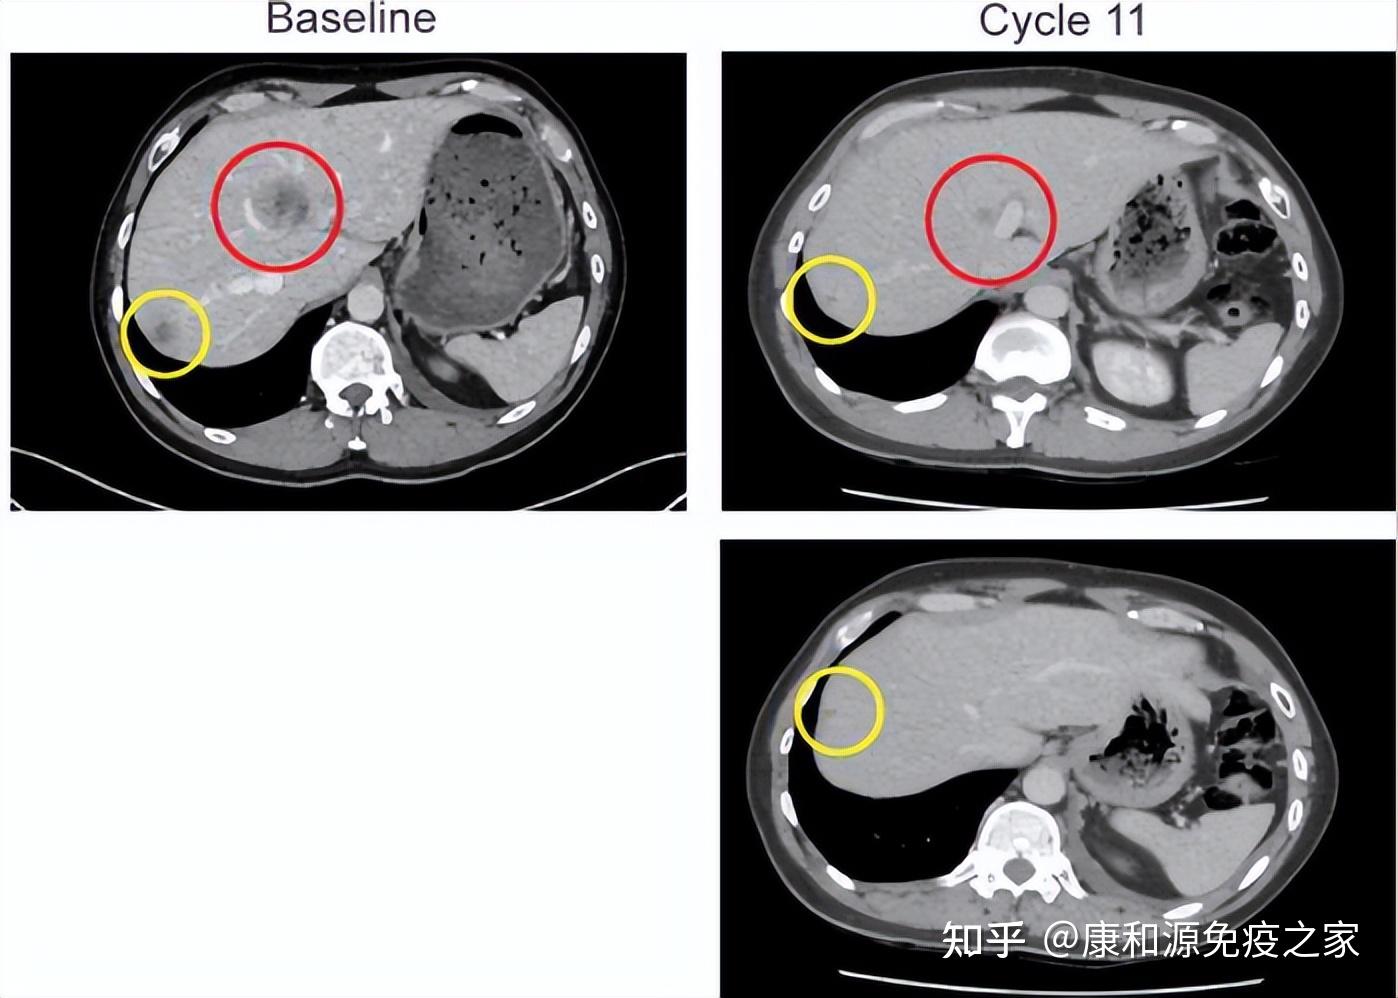

iiia期经过外科,放疗科,肿瘤内科讨论,该病例为潜在可切除iiia肺癌

图片尺寸692x535